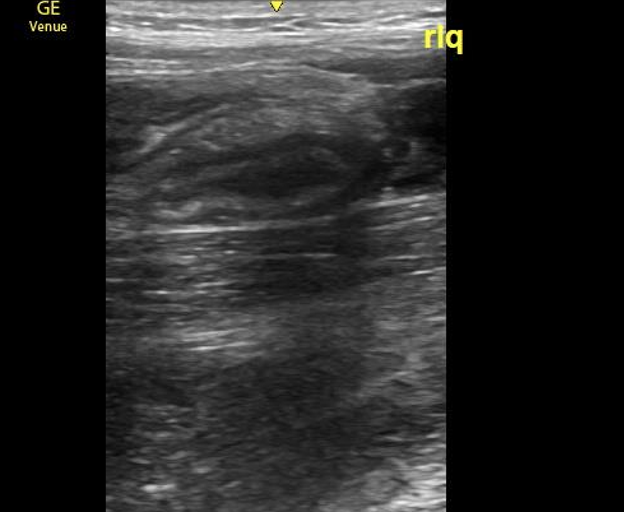

Asking a verbal child where they are experiencing the most pain will likely allow you to begin your exam at a location where the appendix is irritating the peritoneum. (Image 4) The most common anatomic position is a retrocecal or pelvic appendix, so starting in the right lower quadrant is a safe bet.8 Once the point of maximal tenderness is identified, use graded compression to visualize the bowel and evaluate for pathology. “Graded compression” is a technique to gradually put more pressure on the probe to displace the underlying bowel gas to visualize the appendix and assess compressibility. If no appendix is identified at the point of maximal tenderness, move the probe to a transverse RLQ position with the indicator toward the patient’s right, and identify the anatomic landmarks: the iliac vessels and psoas muscle. The appendix is often located ventral or medial to these structures. If you are having trouble finding the relevant anatomy, sometimes beginning in the midline to identify the bladder, and sliding the probe to the patient’s right can help you identify your landmarks of the psoas muscle and iliac vessels more readily. Looking between the bladder and the iliac vessels is also advised to identify a deep pelvic appendix. If the child has a full bladder, it can augment visualization of surrounding structures by providing a better acoustic window.

Image 4. Appendicitis causing irritation peritoneum of the internal oblique and sartorius muscles